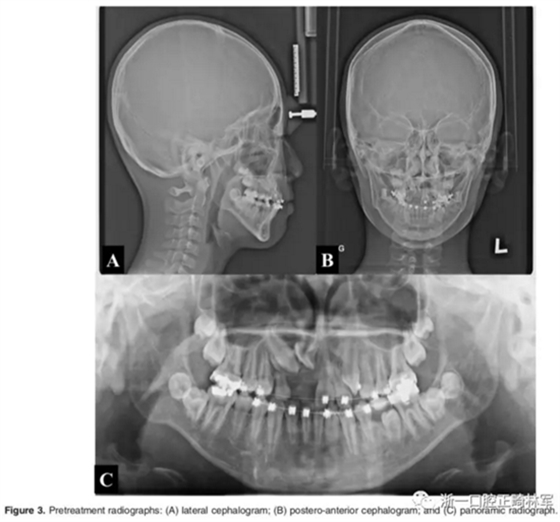

影像檢查:

全景X片及CBCT示:11-13復雜阻生,上頜前牙區(qū)牙槽骨水平不足;11阻生,遠中旋轉90°,牙冠朝向腭側,根尖位于鼻底、前鼻棘皮質骨內,牙根形態(tài)彎曲;12、13不完全易位,12位置偏腭側,13位置偏舌側,12的牙根形態(tài)也較彎曲。

診斷:骨性I類,牙性II類,高角,多牙阻生,面部不對稱(右偏),上下切牙直立。